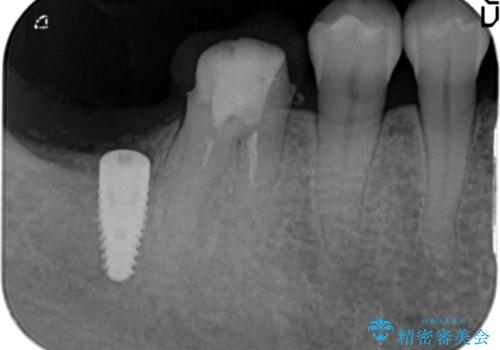

奥歯 インプラントによる機能回復

- 歯を欠損し、噛めないことの治療を希望され来院されました。

インプラントを用いて、しっかりとかめるような治療を計画します。

- 45万円(ストローマンインプラント・骨造成・チタンカスタムアバットメント・ジルコニアクラウン)費用は治療当時の料金となります

奥歯のインプラント治療について

最後方臼歯はインプラントを用いることでしっかりと咬合機能を回復することができます。